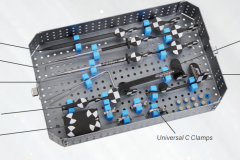

4. Instrument dengan permanent marker yang dapat disteril. TIDAK DIPERLUKAN KALIBRASI INSTRUMEN SETIAP KALI PAKAI